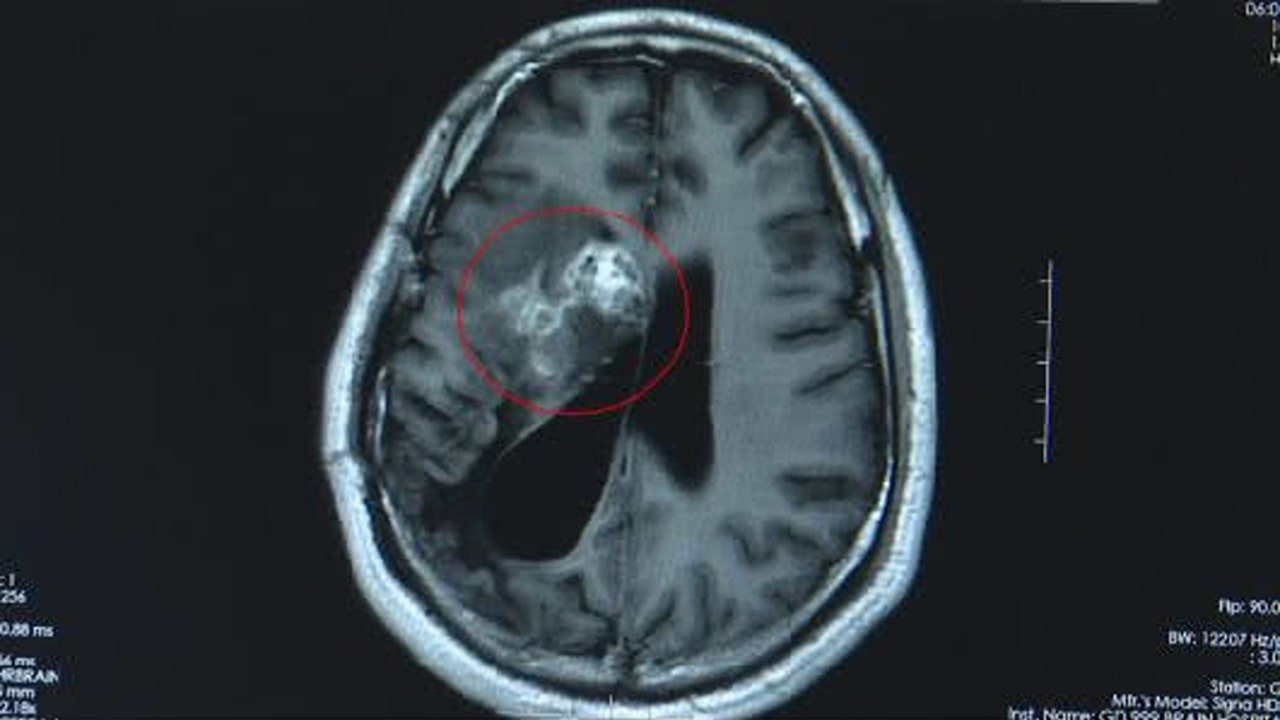

This CT scan shows the tapeworm in Wang's brain. (AsiaWire)

It wasn’t until 2018 that doctors discovered a 12-centimeter Sparganosis parasite in his brain, which is uncommon in humans and typically lives in the intestines of cats and dogs. While the parasite can be found worldwide, most human cases are recorded in Southeast Asian countries.